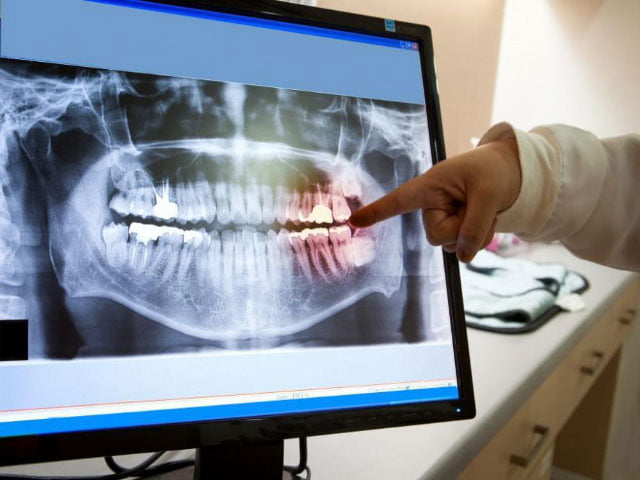

Röntgen çektikten sonra, diş hekimi başın tam bir yan profilini görebilecek. Bu, ortodontik planlamaya yardımcı olabilir ve diş tellerinin yüz profilini ve dişleri nasıl etkileyebileceğinin anında değerlendirilmesine olanak tanır. X-ışını için başka bir yaygın kullanım, diş implantlarının oluşturulması ve yerleştirilmesinden önce belirli ölçümleri belirlemektir. Sefalometrik röntgenler hakkında herhangi bir sorunuz veya endişeniz varsa, lütfen diş hekiminize sorun.